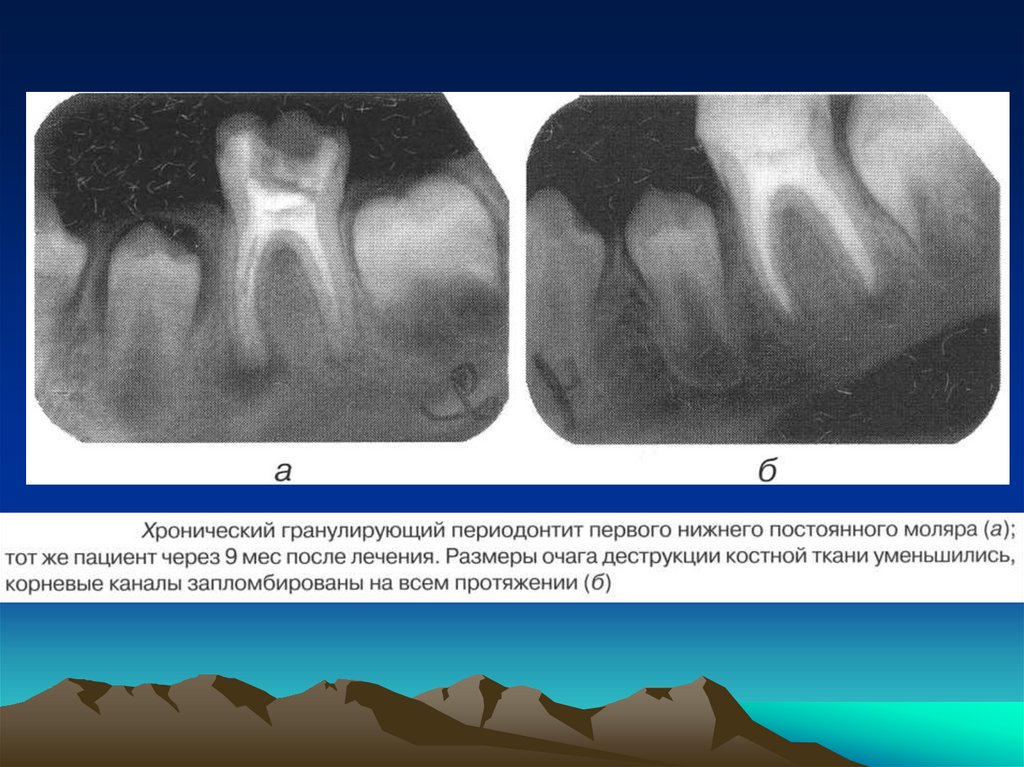

соматического

и